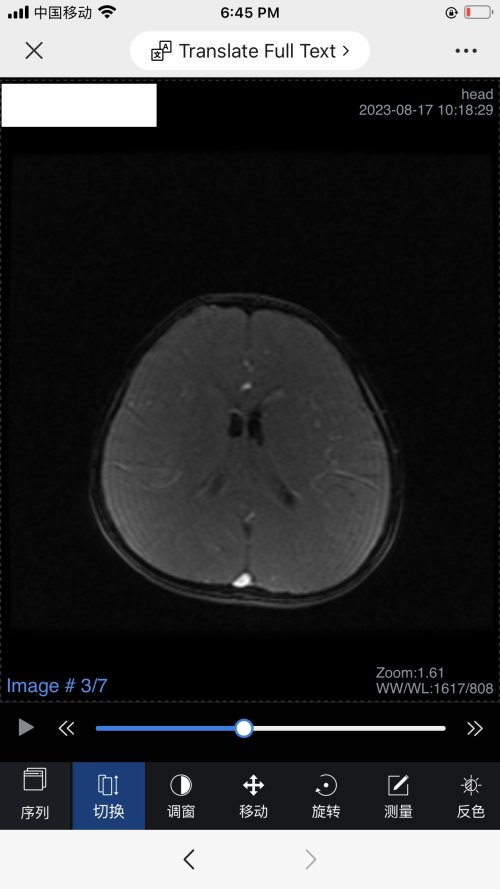

反馈下情况,孩子在国内的医院已经进行过一轮全面检测,没发现什么问题,但是现象是存在的。医生也没什么办法。医生说核磁共振和脑电图没问题,我们也不是很看得懂,各位如果懂的,请指点一下。另外进行了部分基因检测,没发现异常。下一步,我们国庆后打算去更权威的医院去碰碰运气。谢谢各位!

513.6 KB 查看: 103

532.8 KB 查看: 142

551 KB 查看: 132

526.8 KB 查看: 133

510 KB 查看: 103

506.4 KB 查看: 124

495.7 KB 查看: 165